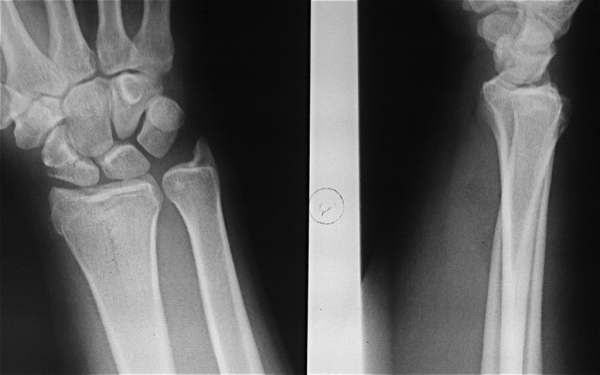

Подборка рентгеновских снимков лучезапястного сустава

Раздел: Объективный взгляд